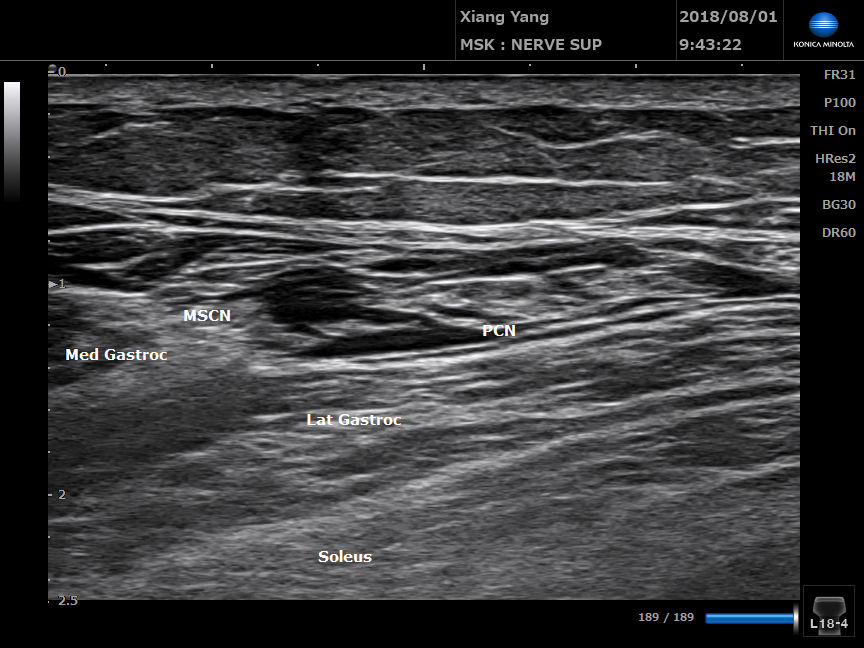

腓腸神經